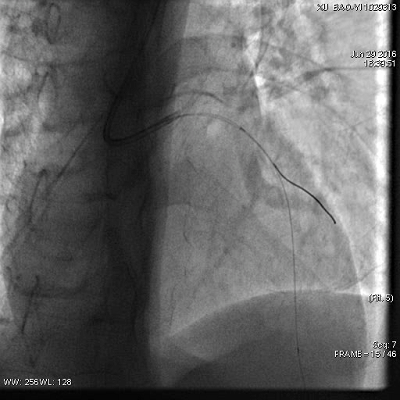

急诊PCI

患者经济原因,仅于前降支中段植入一枚2.5*36mm乐普支架

非罪犯血管病变未处理

6.30凌晨复查冠脉造影